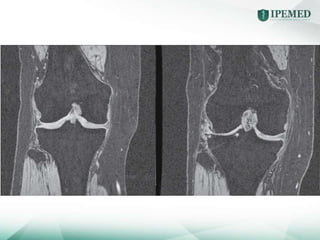

Quatros manifestações:

Estreitamento do espaço articular

Osteófitos

Esclerose subcondral

Cistos subcondrais

Quatros manifestações: Estreitamento doespaço articular Osteófitos Esclerose subcondral Cistos subcondrais • Na OA secundária pode haver alterações da doença primária • NÃO HÁ PARALELISMO CLÍNICO-RADIOLÓGICO